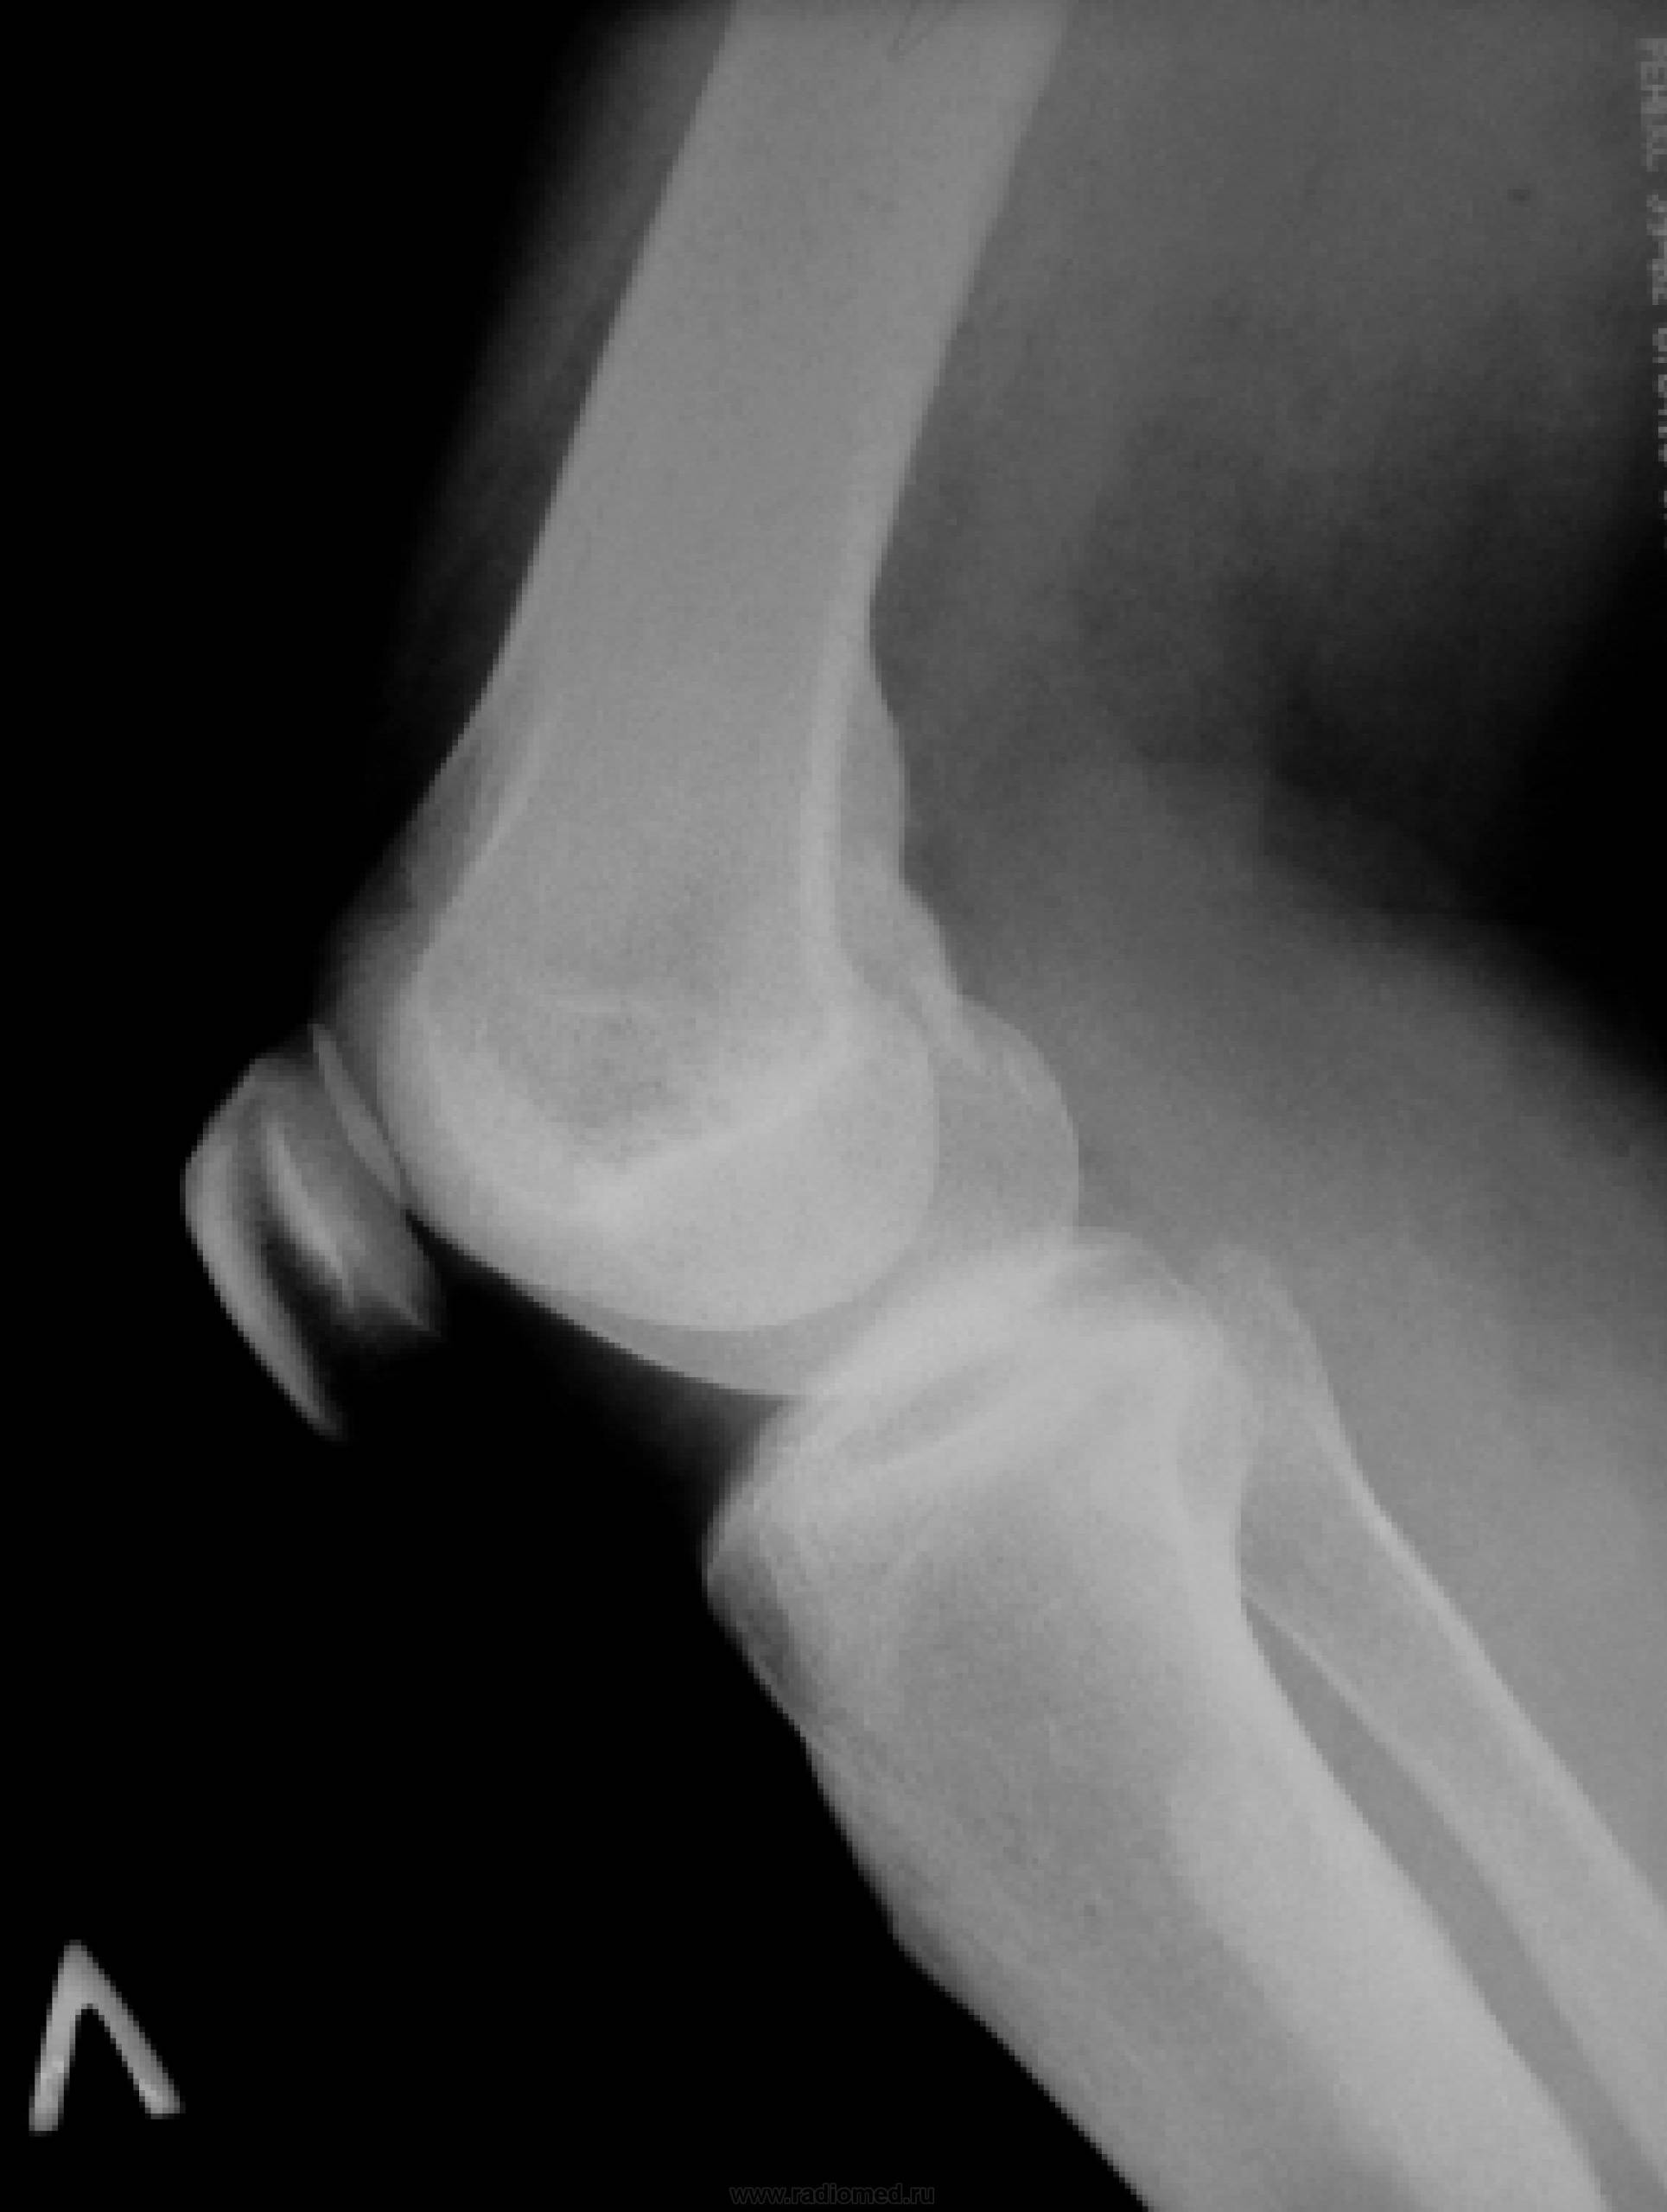

На рентгенологическом снимке можно увидеть типичный очаг «разрежения» костной ткани, вокруг которого развивается зона остеосклероза.

Самый информативный метод диагностики – рентгенологическое исследование. Основными проявлениями остеосклероза являются:

- деформация кости;

- неполный или полный патологический перелом;

- утолщение кости;

- собственно сами очаги остеосклероза.